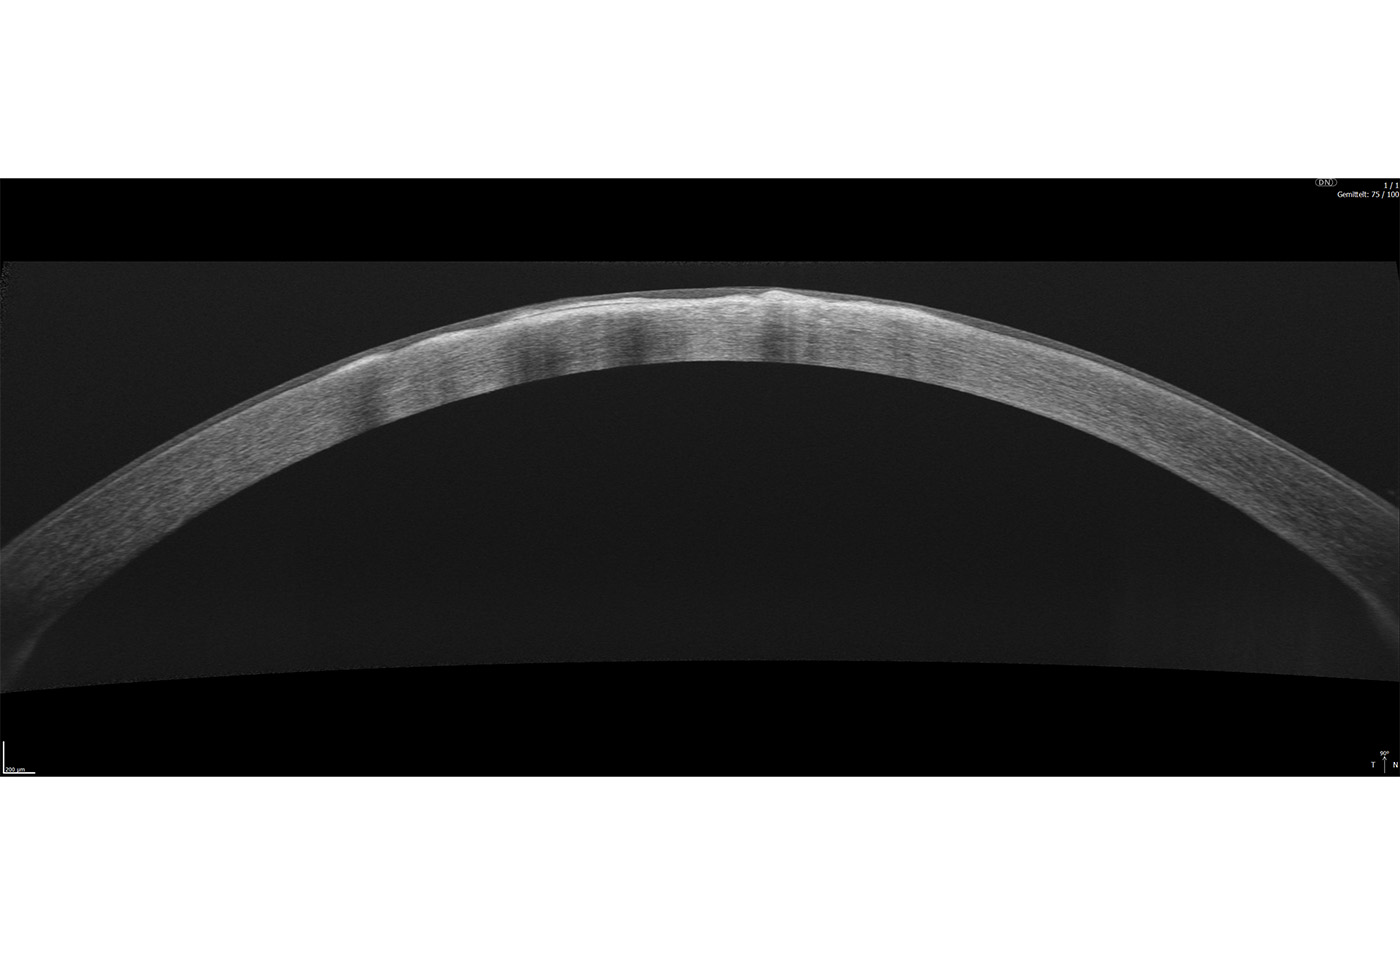

Das Extended Depth Retina Imaging, welches auf der Full Range-Technologie basiert, bietet Scans mit größerer Tiefe für eine zuverlässige und bequeme Kontrolle von schwierigen Fällen. Dank der Scans mit großer Tiefe ist dieser neue Bildgebungsmodus perfekt für die Diagnose von sehr stark kurzsichtigen Patienten geeignet. Außerdem bietet sie einen Überblick über die gesamte Vorderkammer, von Hornhaut bis zur Augenlinse.

- Darstellung des vollständigen vorderen Systems

- Messung beider Kammerwinkel in einer Aufnahme

- Automatische Pachymetrie

- Analyse des Kammerwinkels

- Darstellung der Iris

Zusätzlich existiert ein Scan-Programm zur detaillierten Darstellung der Vorderkammer.

Das OCT-Topographie-Modul (T-OCT) ermöglicht eine umfangreiche Analyse der beiden Grenzflächen der Hornhaut. Zu den wichtigsten Analysen gehören die Ermittlung der Krümmungsradien (K1 und K2) der Hornhaut sowie die daraus resultierende Brechkraft der Hornhaut. Die Werte vervollständigen das in Version 8.0 veröffentlichte OCT-Biometrie Modul (B-OCT) der Copernicus REVO Reihe. Für die Auswertung der Ergebnisse stehen eine Vielzahl unterschiedlichster Darstellungen zur Verfügung. Die T-OCT-Technologie basiert auf dem Prinzip des Ray Tracings. Dabei wird neben der Vorder- und Rückfläche der Hornhaut auch die korrespondierende Hornhautdicke ermittelt. (Optionales Modul)